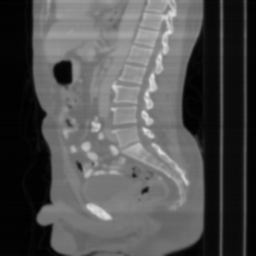

| Ground Truth | Input | DDS-100 [chungdecomposed] | DDS-200 [chungdecomposed] | NERD-P (Ours) |

![]() |

| PSNR = dB | PSNR = 14.56 dB | PSNR = 37.42 dB | PSNR = 37.81 dB | PSNR = 39.15 dB |

Main results: In Table 1, we present quantitative results and in Figure 2, we show visualizations in the axial, coronal, and sagittal planes. Our methods consistently outperform the second-best baseline across most views, achieving nearly 1 dB higher PSNR on average. Despite incorporating a few additional input updates to enforce data consistency, our method reaches competitive performance with only 30 sampling steps. Based on the visualizations, we observe that DDS introduces slight artifacts along the horizontal direction, particularly noticeable in the coronal and sagittal views. In contrast, our method produces cleaner reconstructions with fewer artifacts in these orientations.